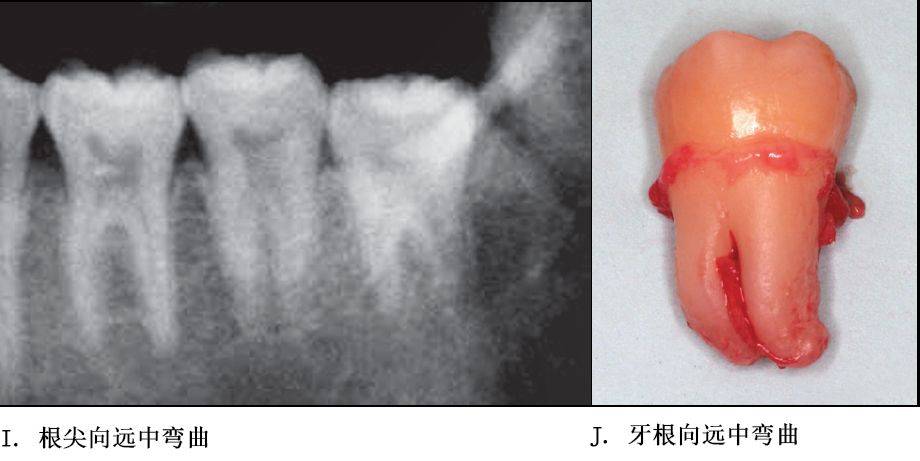

单根牙、根分叉不大者、合并根、融合根、特短根、锥形根阻力较小。若根尖区向远中弯曲、无弯曲或根尖未形成,则阻力也较小。

根部阻力较小的智齿形态